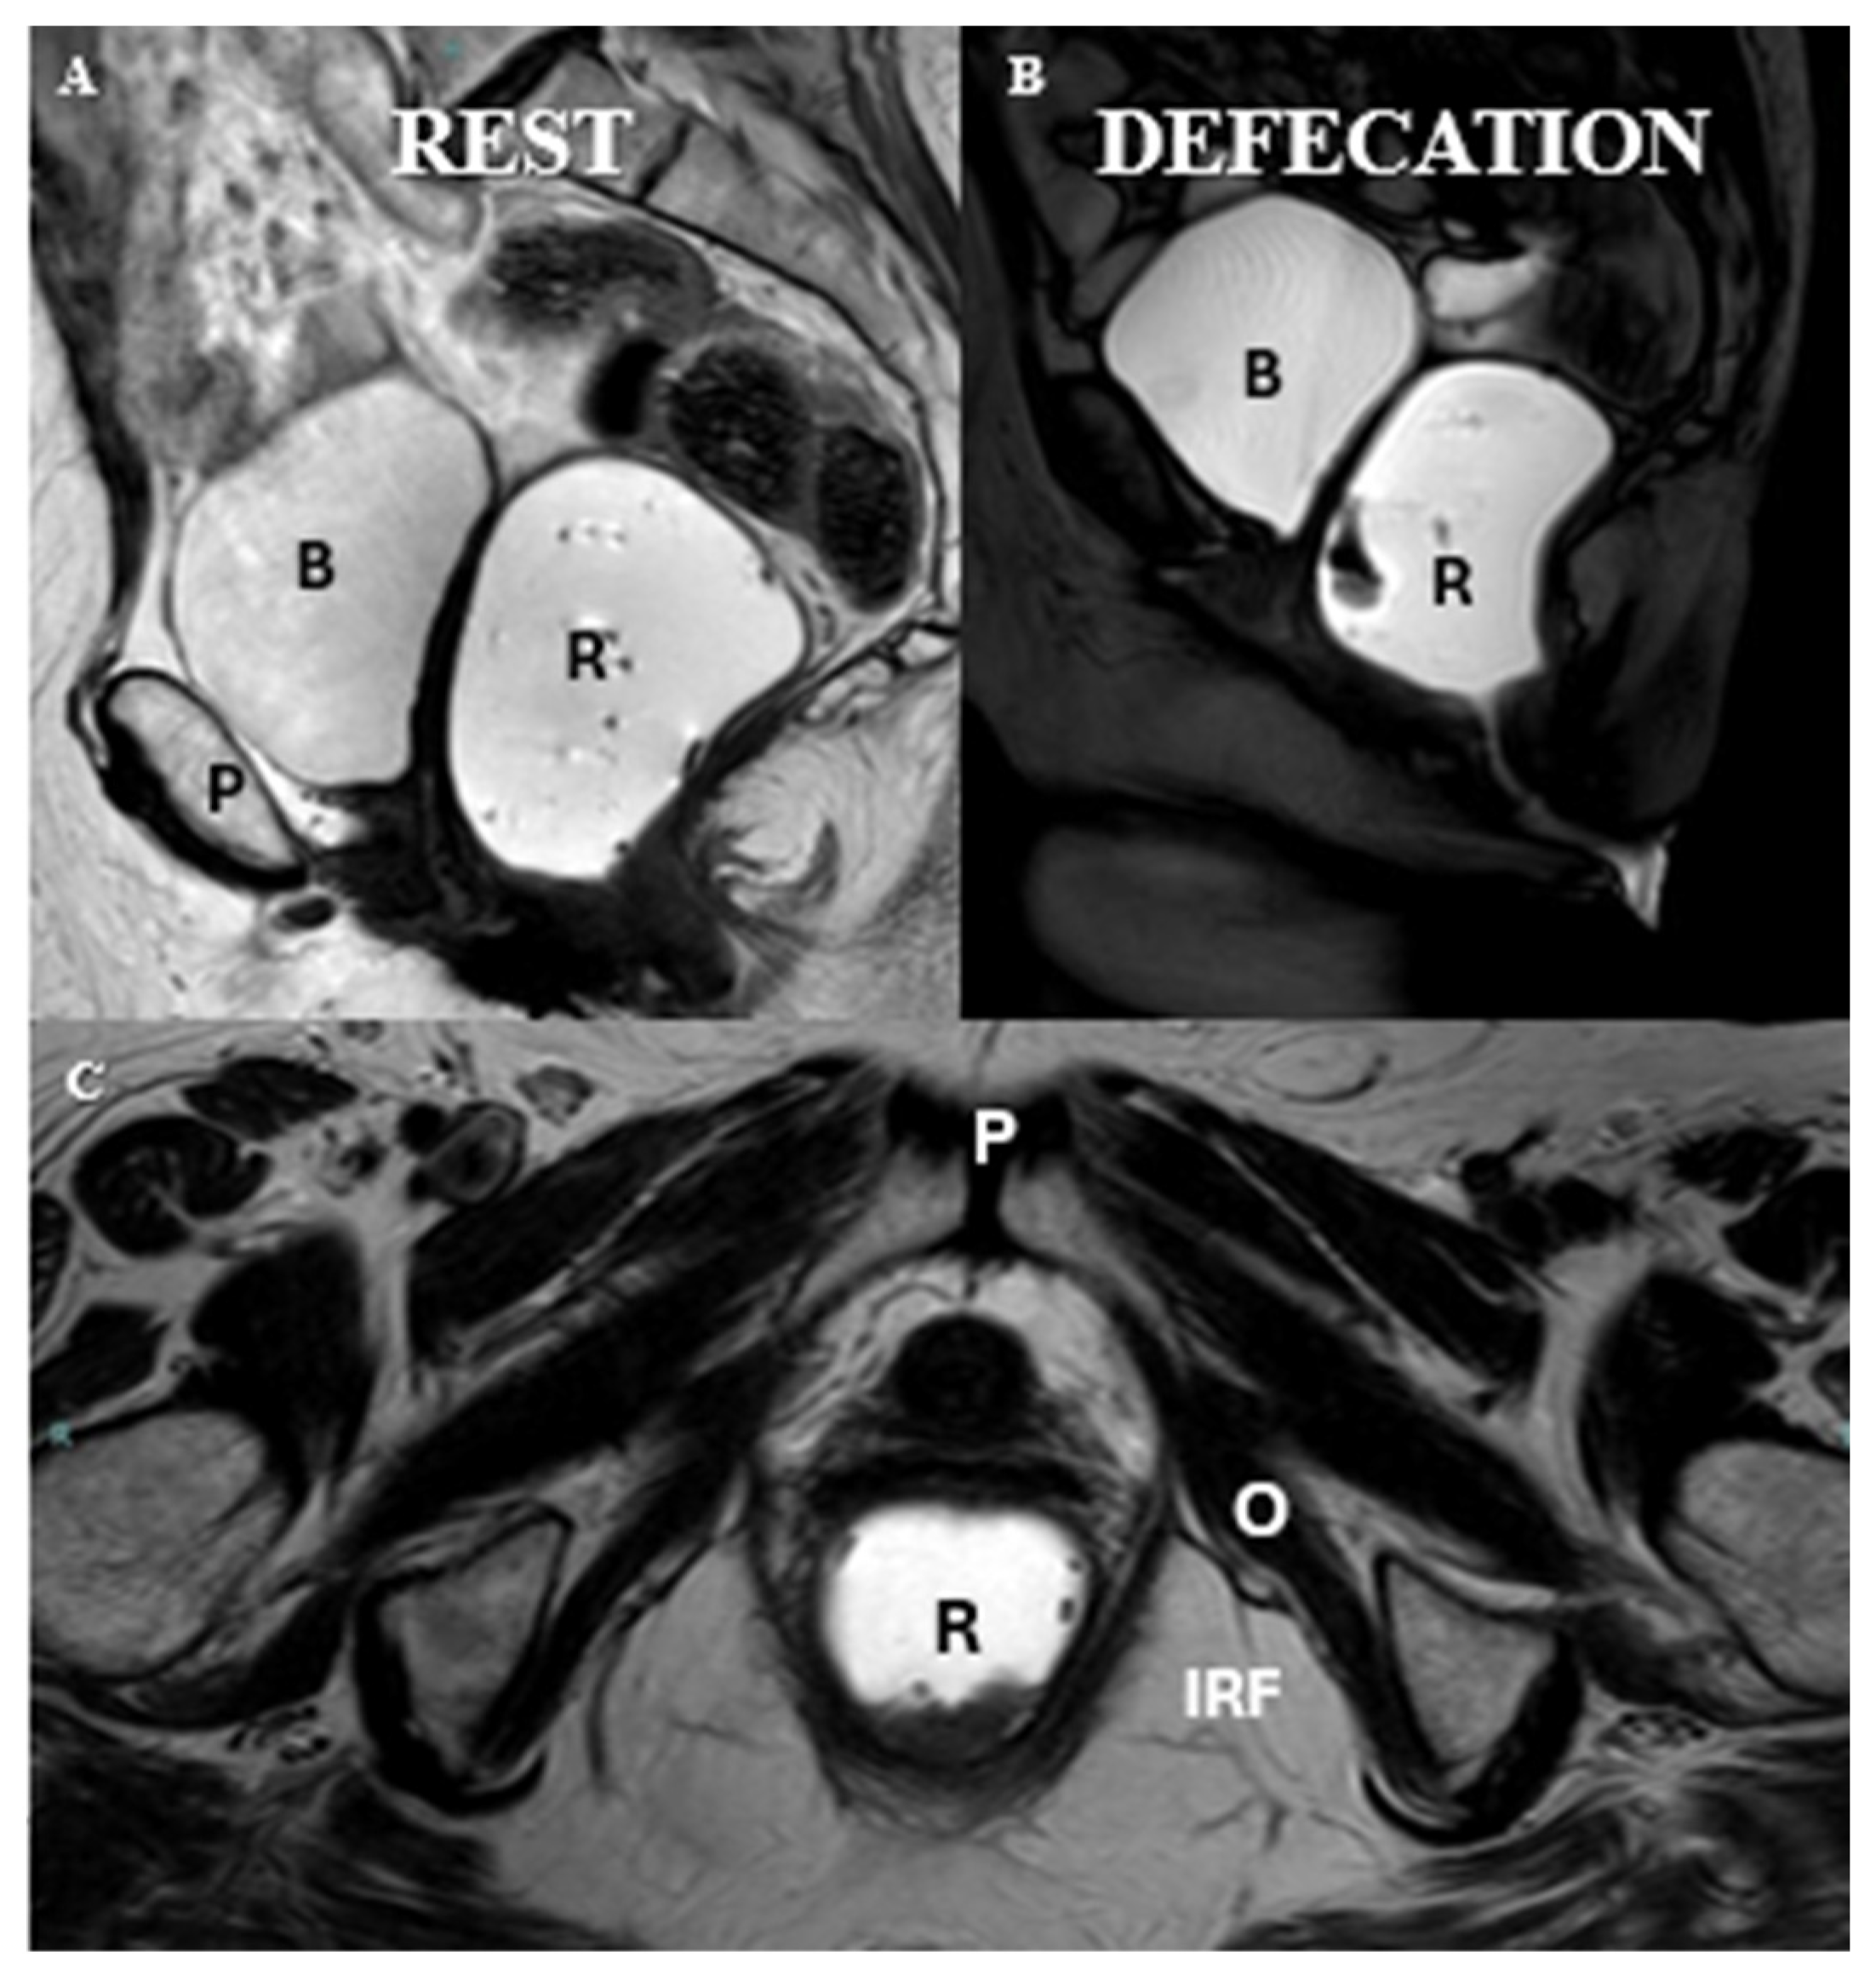

- Salvador, J.C.; Coutinho, M.P.; Venâncio, J.M.; Viamonte, B. Dynamic magnetic resonance imaging of the female pelvic floor-a pictorial review. Insights Imaging 2019, 10, 4. [Google Scholar] [CrossRef]

- Pannu, H.K.; Kaufman, H.S.; Cundiff, G.W.; Genadry, R.; Bluemke, D.A.; Fishman, E.K. Dynamic MR imag-ing of pelvic organ prolapse: Spectrum of abnor-malities. Radiographics 2000, 20, 1567–1582. [Google Scholar] [CrossRef]

- Ghafoor, S.; Beintner-Skawran, S.M.; Stöckli, G.; Betschart, C.; Reiner, C.S. Pelvic organ movements in asymptomatic nulliparous and symptomatic premenopausal women with pelvic organ prolapse in dynamic MRI: A feasibility study comparing midsagittal single-slice with multi-slice sequences. Abdom. Radiol. 2023, 48, 2658–2671. [Google Scholar] [CrossRef]